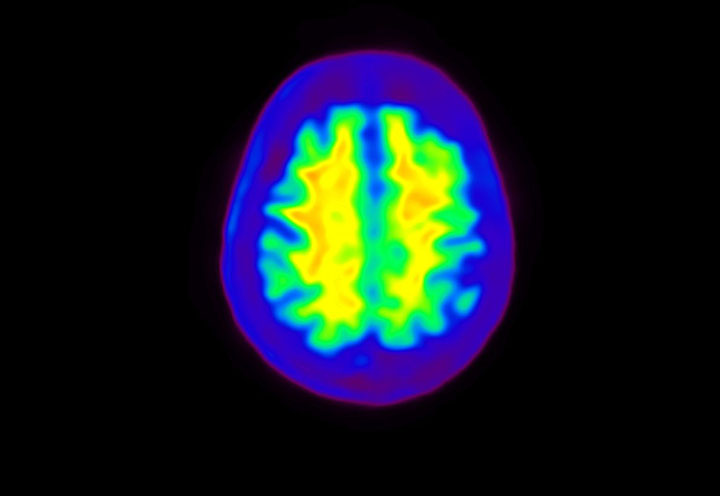

Head / Case4 : Amyloid

Axial

Courtesy : Kindai University Hospital

- Imaging protocol

- Injected dose: 3.21 MBq/kg, 18F-Flutemetamol

- Uptake time: 100 minutes

- Scan time: 20 minutes